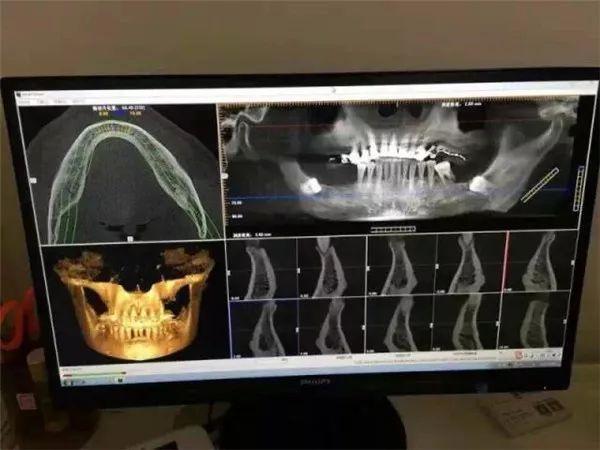

這臺(tái)堪稱口腔界“愛馬仕”的德國(guó)卡瓦CT機(jī)

進(jìn)一步提升整體診療水平

全新的三維影像系統(tǒng),360度旋轉(zhuǎn)閱片模式

高清晰3D影像圖片質(zhì)量為你提高

更清晰直觀,更準(zhǔn)確,更,更的診斷

讓不是醫(yī)生的你也能看懂專業(yè)的影像

1、拍攝CT

經(jīng)過一系列的基礎(chǔ)檢查

蘇志丹的身體狀況適合進(jìn)行種植手術(shù)

但是具體要用什么樣的種植方案

還需要經(jīng)過這臺(tái)德國(guó)卡瓦CT機(jī)

的“火眼金睛”仔細(xì)查看

只需要安靜地坐著

機(jī)器會(huì)通過對(duì)患者360°旋轉(zhuǎn)掃描

獲得三維圖像

“第一次體驗(yàn)這臺(tái)德國(guó)卡瓦CT機(jī),感覺很神奇,機(jī)器自己的旋轉(zhuǎn),就可以把我口腔情況一覽無(wú)遺?!?/p>

電腦同步得到卡瓦機(jī)掃描的數(shù)據(jù)

利用德國(guó)卡瓦CT機(jī)判斷

全口牙床的位置、牙槽骨的高度和深度等

醫(yī)生可在計(jì)算機(jī)上清楚判讀出牙槽骨的情況

重建成3D數(shù)字模型